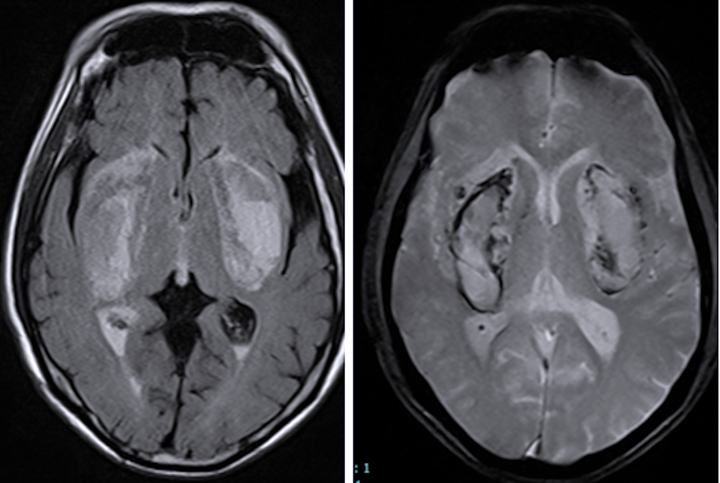

Kết quả chụp cộng hưởng từ sọ não cho thấy có tổn thương nhồi máu, hoại tử, chảy máu nhân bèo hai bên – dạng tổn thương não điển hình do ngộ độc methanol. Dù được hồi sức tích cực, lọc máu, thở máy nhưng tình trạng người bệnh vẫn rất nặng, hôn mê sâu, có nhiều nguy cơ lâm vào tình trạng sống thực vật.